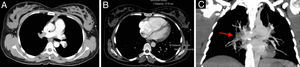

Objetivamente, apresentava-se agitada com hipotensão (73/35mmHg), taquicardia (115 bpm), hipoxémia (saturação de O2 em ar ambiente 80%) e polipneia (50 cpm). Sem sinais de trombose venosa profunda (TVP). Fez análises (hemoglobina 12,3g/dL; plaquetas 170x109/L; d-dímeros 2.962 ng/mL e troponina I 0,43 ng/mL (referência <1,50 ng/mL)) e na gasometria arterial realizada já com O2 suplementar a 5 L/min apresentava alcalose respiratória (pH 7,49; pO2 105mmHg; pCO2 28mmHg, HCO3− 20,9 mmol/L e saturação de O2 98%). Realizou eletrocardiograma (ECG), que mostrou taquicardia sinusal e sinais de sobrecarga no ventrículo direito (VD) (Figura 1) confirmados por ecocardiograma transtorácico (ETT) à cabeceira (Figura 2).

(A) Trombo oclusivo na artéria pulmonar direita, que se estende aos seus ramos lobares. À esquerda existe trombo oclusivo na artéria lobar superior, que se estende à artéria pulmonar esquerda. Existe também trombo na artéria lobar inferior, não totalmente oclusivo, que se estende aos seus ramos segmentares. (B) Ventrículo direito com 57mm e ventrículo esquerdo com 29mm. (C) Reconstrução no plano coronal em corte espesso (24mm) com reformatação em MIP (maximum intensity projection) com trombo na artéria pulmonar direita (seta vermelha).